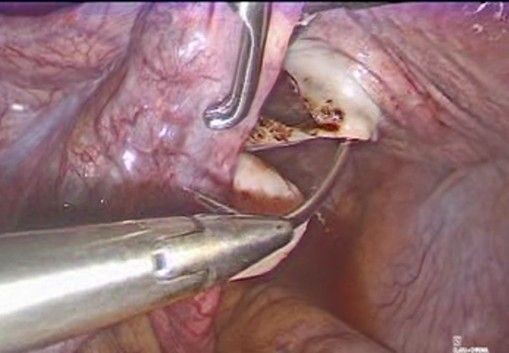

A 36-year-old female patient, G2 P1 A1, with no significant medical history. Her first pregnancy ended with a cesarean section at 27 weeks due to cervical incompetence, with a newborn weighing 850 g. She subsequently suffered an incomplete miscarriage at 19 weeks, also secondary to cervical incompetence, resolved by instrumental uterine curettage. Given the clear history of cervical incompetence, a laparoscopic transabdominal Benson-Durfee cerclage was performed. The procedure was performed without complications, the procedure lasted 60 minutes, a V Care type uterine mobilizer was used, with an estimated blood loss of 100 ml, and she was discharged the following day. Subsequently, the patient continued with follow-up and ultrasound confirmed the correct placement of the cerclage. (Figure 1).

Figure 1: Green arrow: correct placement of the cerclage